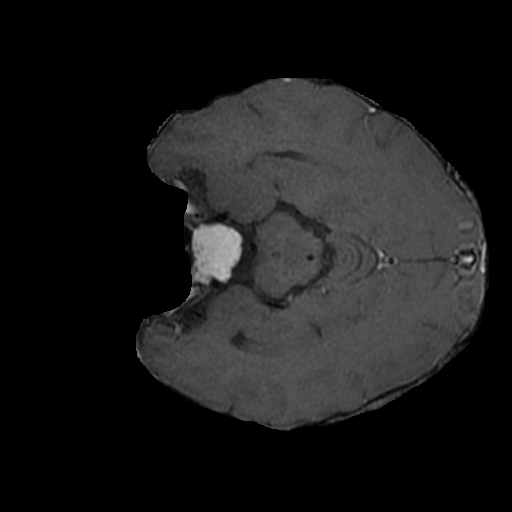

In this current work, extensive experiments have been carried out on Dynamic Susceptibility Contrast (DSC) brain MR images of Glioma patients from TCIA data sets of size using Nvidia RTX 2070 GPU System with high-performance systems with MATLAB 2020a and Python 3.6. The 2D segmented images are processed through a 2D binary circular mask to obtain the brain lesion in the suggested QFS-Net framework. The lesion or brain tumor detection mask is binarized using a threshold of , and in the case of QFS-Net and QIS-Net [39], it is seen that with a radius of pixels, the segmented ROIs perform optimally while compared with the human expert segmented images. Experiments are also performed on two recently developed CNN architectures suitable for medical image segmentation viz., convolutional U-Net [18] and Residual U-Net (URes-Net) [20] available in GitHub. The U-Net and URes-Net networks are rigorously trained using the stochastic gradient descent algorithm with learning rate and batch size allowing maximum epochs to converge. The segmented output images resemble in size with the dimensions of the binary mask and the outcome is considered as tumor region and as background in detecting complete tumor. The pixel by pixel comparison with the manually segmented regions of interest or lesion mask allows evaluating the dice similarity, which is considered as a standard evaluation procedure in automatic medical image segmentation. The evaluation process involves the manually segmented lesion mask as ground truth, and each 2D pixel is predicted as either True Positive () or True Negative () or False Positive () or False Negative ().

Extensive experiments have been performed in the current setup, and experimental outcomes are reported with the demonstration of numerical and statistical analyses using the proposed QFS-Net, QIS-Net [39], convolutional U-Net [18] and Residual U-Net (URes-Net) architectures [20]. The human expert segmented skull-tripped contrast enhanced DSC brain MR input image slices of size and ROIs are provided in Figure 5 as samples. The demonstration of QFS-Net segmented images followed by the essential post-processed outcome on the slice no. for class level with four distinct activation schemes () are shown in Figure 6. It is evident from the experimental data provided in Table LABEL:tab1 that the proposed QFS-Net performs optimally for the -connected quantum fuzzy pixel information heterogeneity assisted activation () with and gray scale set in comparison with other thresholding schemes and gray scale sets under the four evaluation parameters () [44]. The segmented tumors obtained using the proposed self-supervised procedure under class transition levels with four different thresholding schemes , , and are demonstrated in Figures 7- 8 for the class boundary sets and [39], respectively. The segmented images using the remaining two class boundary sets ( and ) [39] are provided in the supplementary materials section. The segmented ROIs describing the whole tumor region after the masking procedure using QIS-Net, U-Net and URes-Net are also reported in Figure 9.